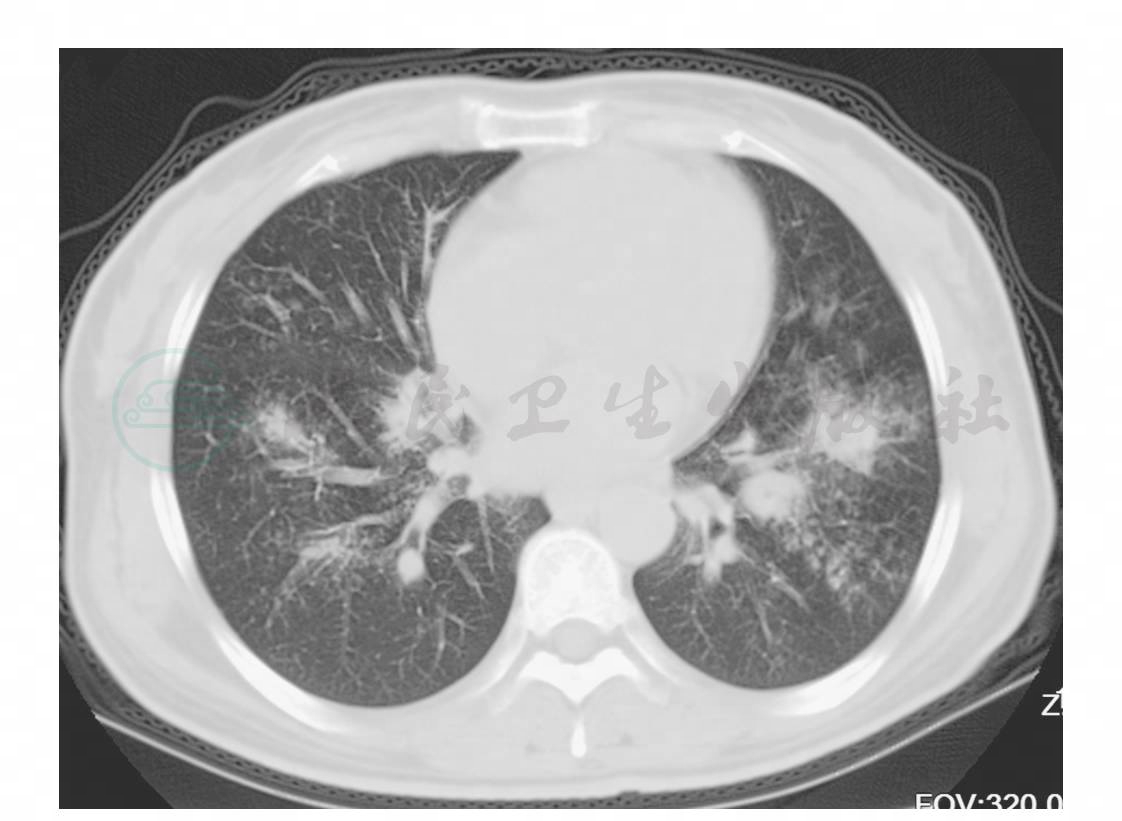

图2 胸部CT(2009年12月31日)

入院后查胸部CT示两肺散在斑片影,考虑炎症(图2),予头孢西丁、阿奇霉素抗感染及祛痰、止咳等对症治疗。症状改善不明显。监测血糖时有波动,调整胰岛素用量,另予阿卡波糖口服加强控制血糖。查结核抗体阳性,但多次痰找抗酸杆菌阴性。于2010年1月12日行纤维支气管镜检查示左上叶尖后段、左下外基底段及右下叶内基底段管腔内见黄白色物质(图3)。于左下叶外基底段行活检,物质质地较硬,少有出血,钳取物送病理检查。左下叶外基底段行支气管肺泡灌洗,送抗酸菌及细胞学检查。于左上叶上舌段、左下叶外基底段及右下叶内基底段行刷检,送抗酸菌及细胞学检查。纤维支气管镜刷检及支气管肺泡灌洗液(BALF)找抗酸杆菌阴性。病理结果为(支气管黏膜)慢性炎伴曲霉感染,部分组织挤压(图4)。GM试验0.36。